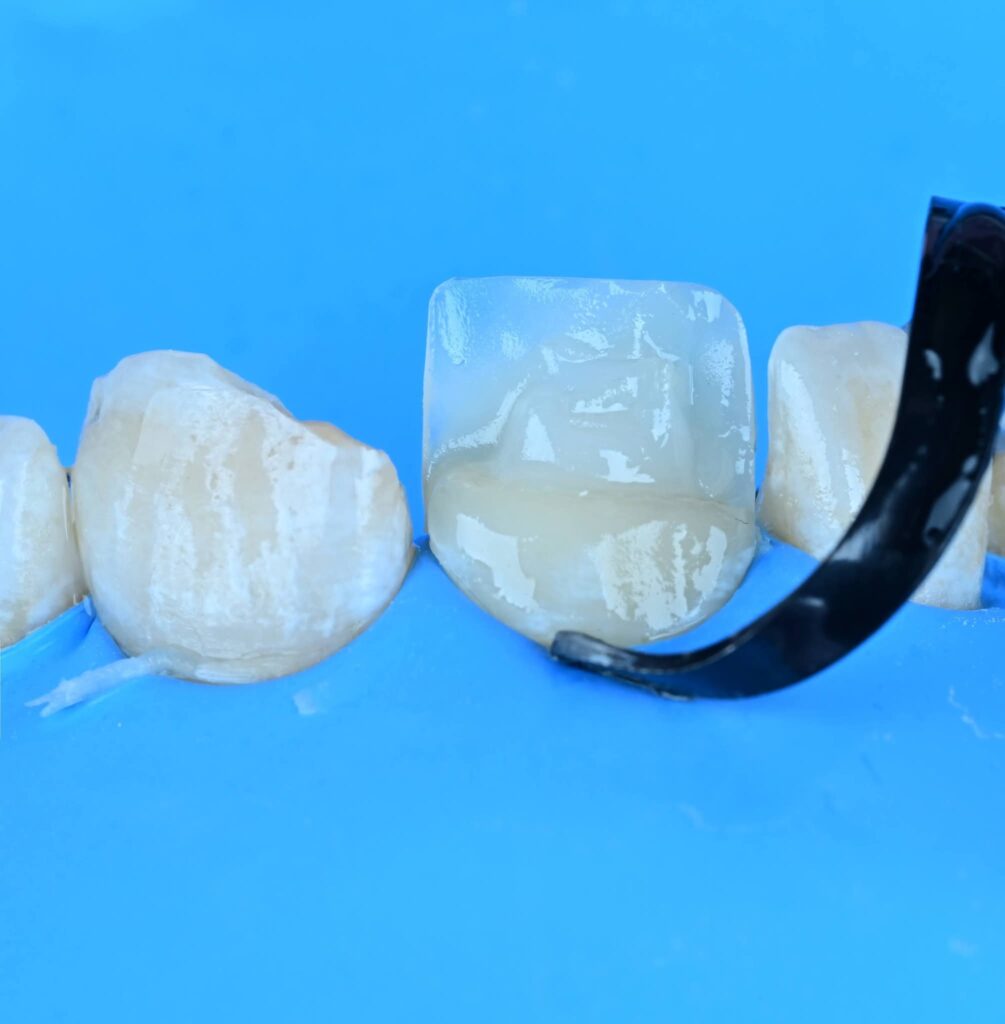

Symmetry and proportionality are fundamental principles in aesthetic dentistry, particularly in direct composite veneers, where the clinician acts simultaneously as a scientist and an artist. Successful veneers are not determined only by color and shape, but by the harmony between teeth, gingiva, lips, and face.

3. Surface texture and light reflection

4. Incisal translucency and halo effects